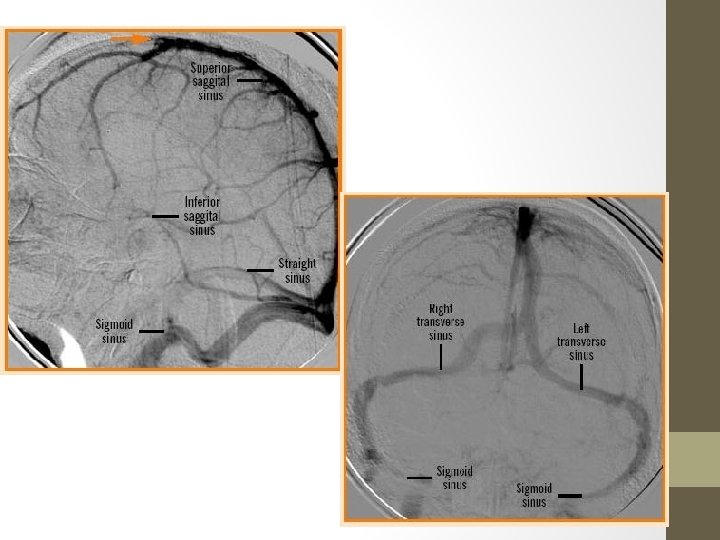

• The cerebral venous system, unlike the majority of the rest of the body, does not even remotely follow the cerebral arterial system • The cortical veins lie superficially, unlike cortical arteries, and are adherent to the deep surface of the arachnoid so that they keep the sulci open • Cortical veins then drain to the nearest dural venous sinuses. Such as the superior sagittal sinus and the straight sinus to the confluence of sinuses, then to the transverse sinuses, sigmoid sinuses and internal jugular veins.

Deep Cerebral Veins • Drain deeper parts of hemispheres, basal nuclei, internal capsule, diencephalon and choroid plexus • Consists of the lateral sinuses, sigmoid sinuses, straight sinus and draining deep cerebral veins (subependymal and medullary veins) -Medullary veins are numerous and originate 1 -2 cm below cortical gray matter and pass through deep medullary white matter and drain into subependymal veins. -Subependymal veins receive medullary veins and aggregate into greater tributaries, mainly into septal veins, thalamostriate veins, internal cerebral veins, basal vein of Rosenthal and vein of Galen.

Dural Venous Sinuses • Venous channels located intracranially between the two layers of dura mater (endosteal layer and meningeal layer) • Unlike other veins in the body they run alone, not parallel to arteries • They are valveless, allowing for bidirectional blood flow in intracranial veins. • Together the dural venous sinuses form the major drainage pathways from the brain, predominantly to the internal jugular veins. • https: //www. youtube. com/watch? v=Dc-z 7 b. DD-KM